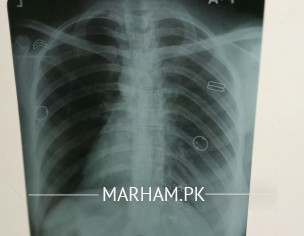

Kindly do comment on chest x-ray of my sister

normal

ulti tasveer hy

seems normal